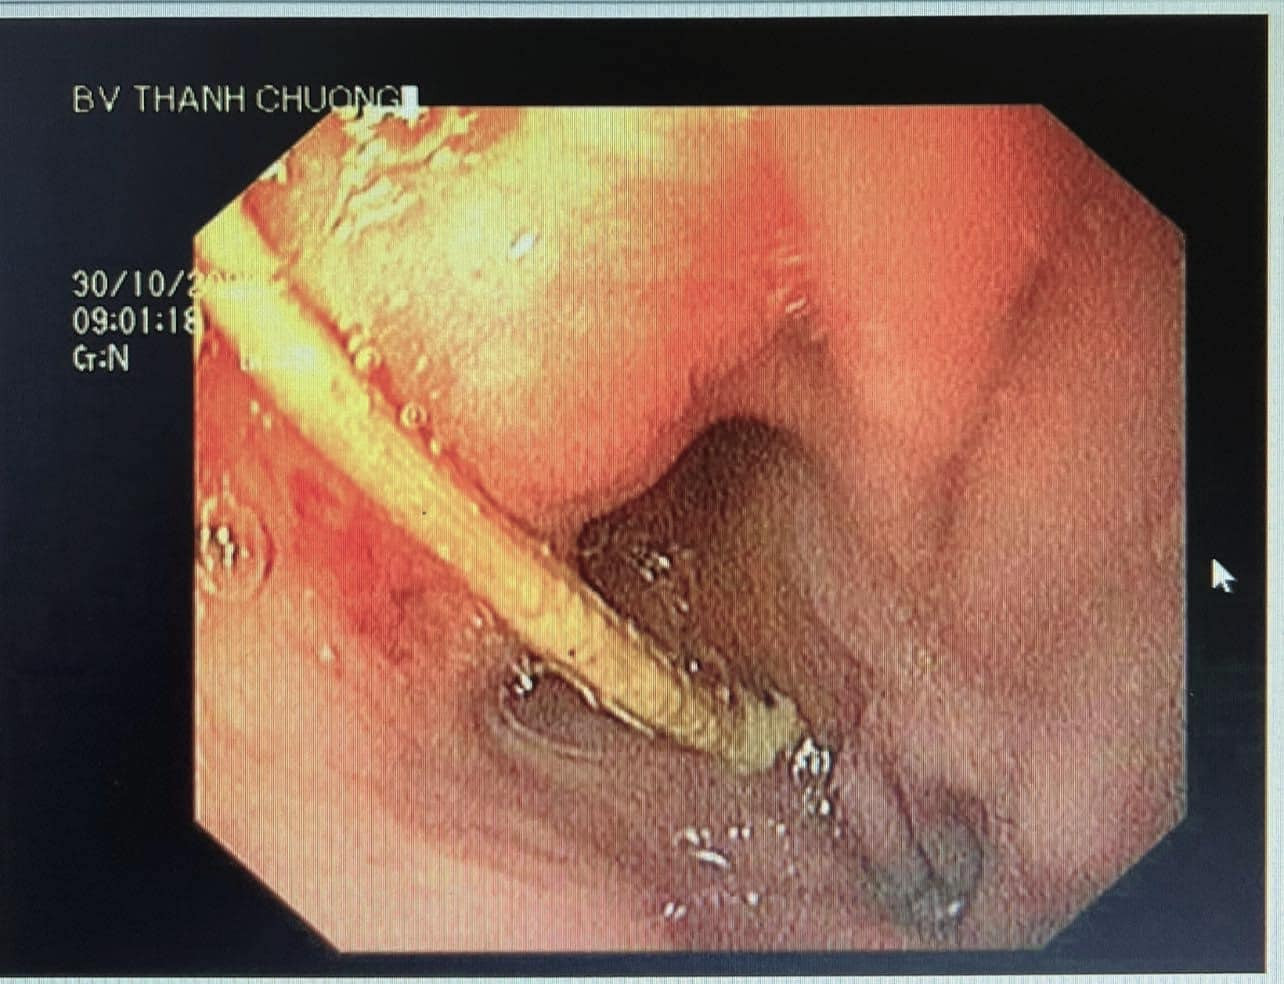

| Hình ảnh nội soi que tăm dài 5cm trong dạ dày bệnh nhân. |

Qua thăm khám, bác sĩ đã chẩn đoán và chỉ định nội soi tiêu hoá. Trong quá trình nội soi dạ dày, bác sỹ phát hiện thấy gần môn vị dạ dày có 1 que tăm tre (còn nguyên 2 đầu nhọn) đâm vào thành dạ dày gây viêm loét. Các bác sỹ sau đó đã tiến hành nội soi dạ dày bằng phương pháp gây mê và gắp thành công que tăm tre dài khoảng 5 cm ra ngoài an toàn. Sau gắp lấy dị vật ra ngoài, bệnh nhân T. ổn định sức khỏe và xuất viện về nhà.